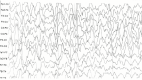

Figure 1. Abnormal EEG shows neurodegenerative changes.